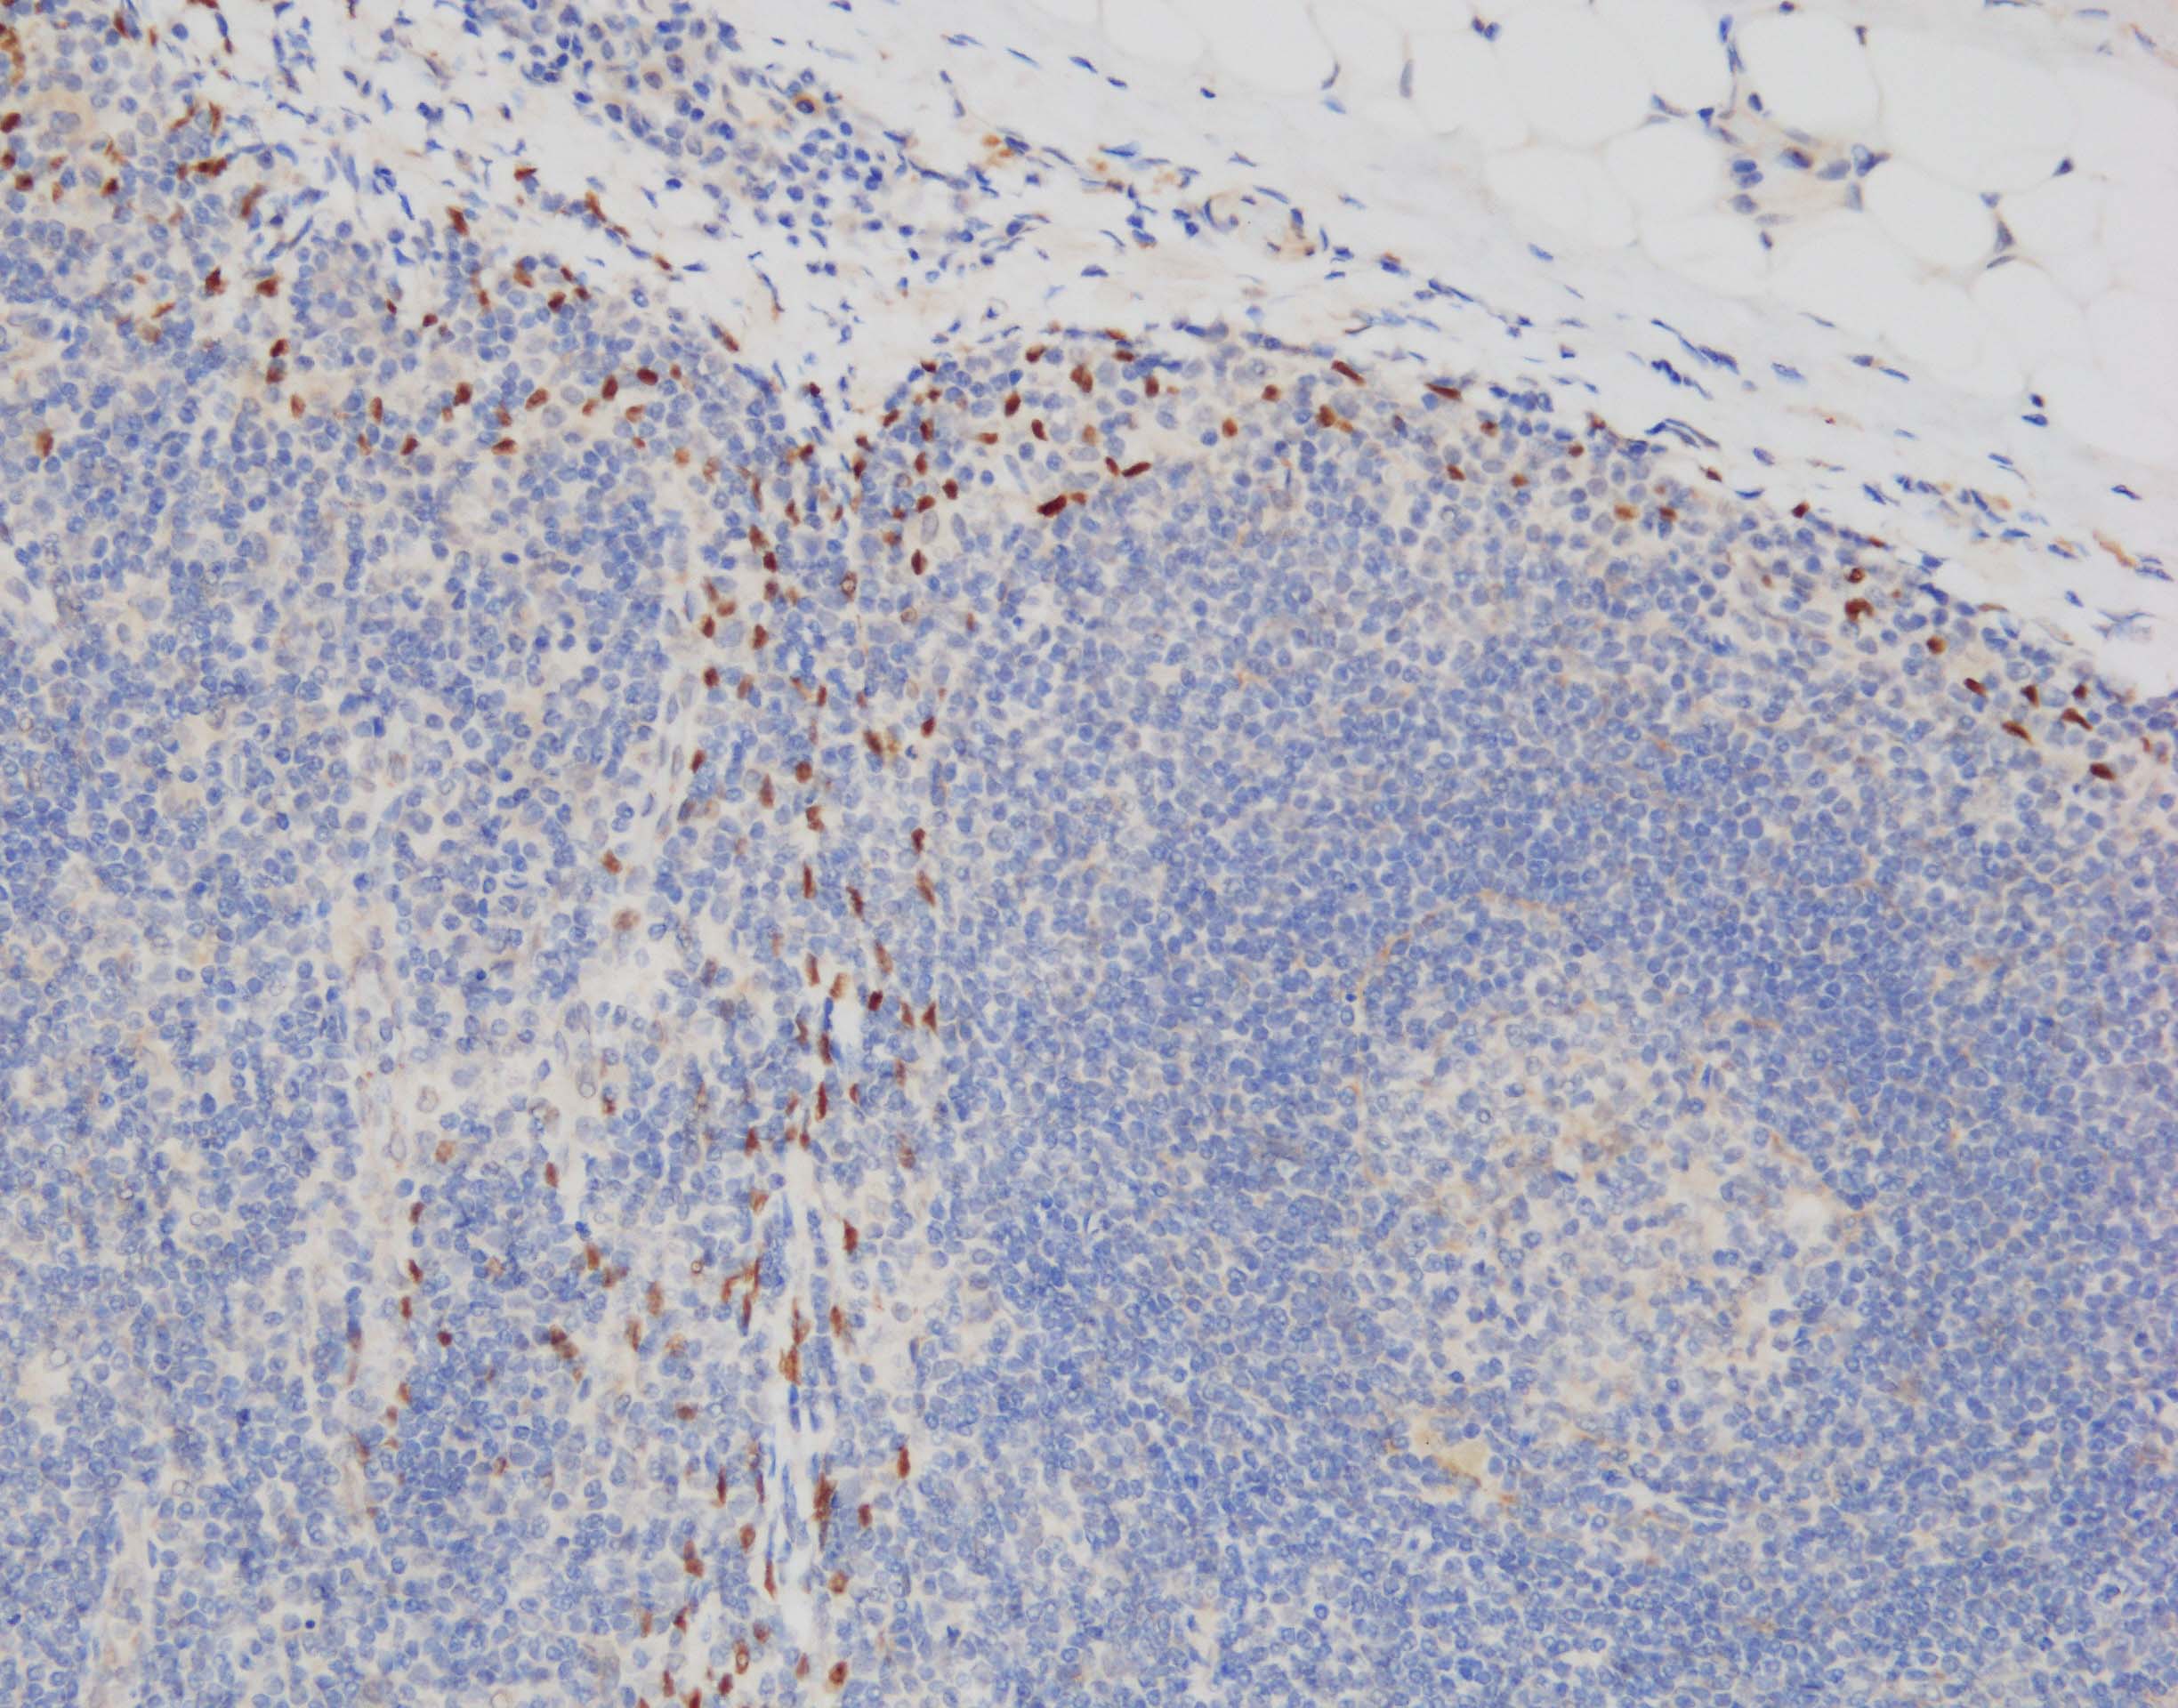

IHC-P: pH 9 antigen retrieval, primary Ab x50 30min, HRP-polymer detection system + DAB